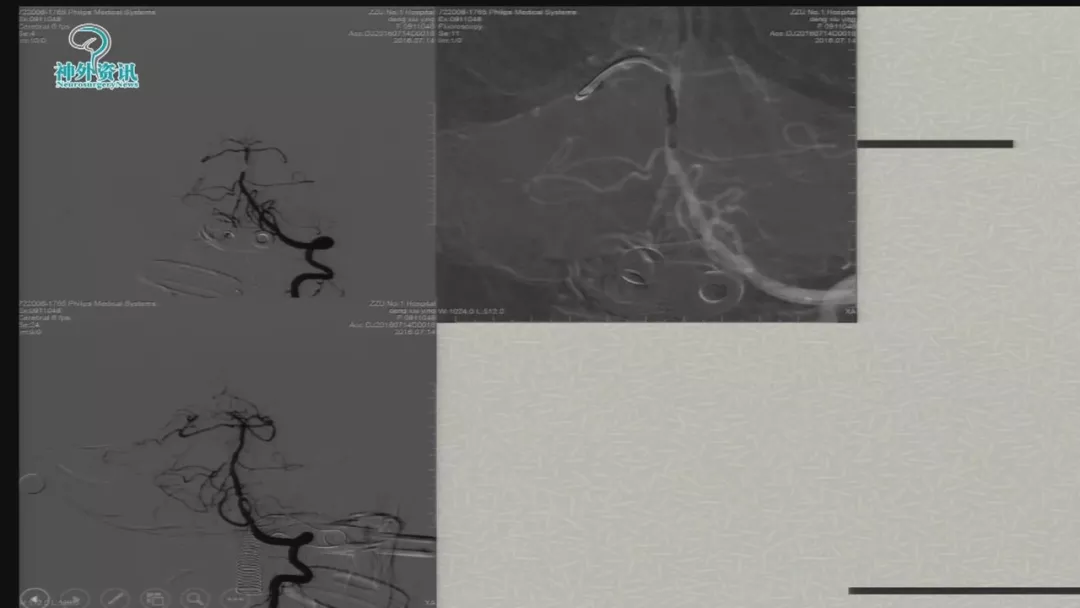

今天为大家分享的是由郑大一附院徐浩文教授在第七届全国介入医学工程大会上带来的“Neuroform EZ在ICAD治疗中的应用”精彩讲课视频和PPT,欢迎观看!(内容未经讲者审核,不当之处请与我们联系)